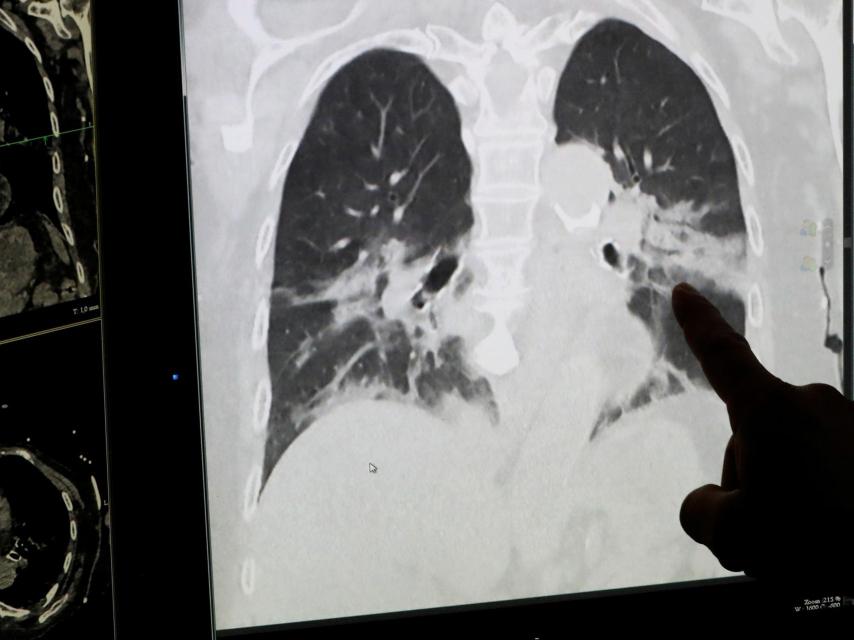

Un radiólogo muestra unos pulmones infectados por Covid-19.

Un radiólogo muestra unos pulmones infectados por Covid-19. Yves Herman Reuters